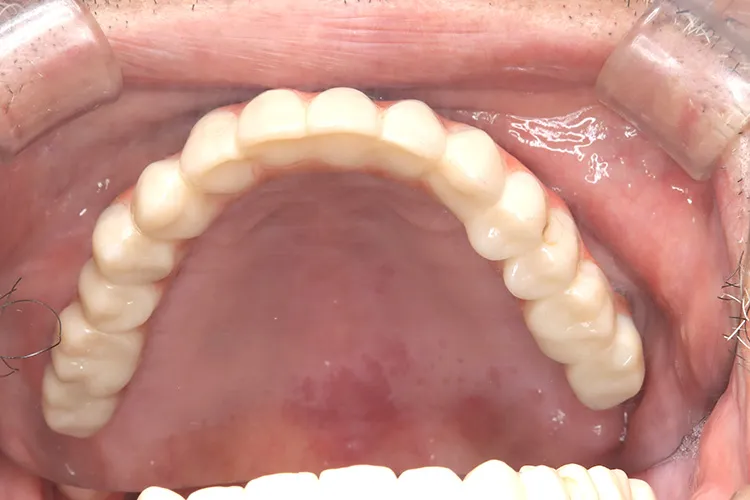

上顎の総入れ歯が不安定で固定式を希望され、インプラント6本で上部構造を支えるボーンアンカードブリッジを選択されました。インプラント埋入したその日にそれまで使用していた入れ歯をインプラントに固定させました。その後歯肉が治癒した段階で最終の上部構造(14本ブリッジ)を装着しました。